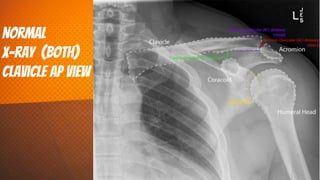

NorMal

x-ray (both)

clavicle AP view